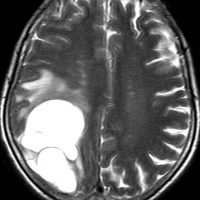

無症状で発見された若年成人の左前頭葉グリオーマです。ガドリニウム(右側)では全く増強されません。手術で全摘出しました。組織像は退形成性星細胞腫でした。壊死も血管内皮増生,多核巨細胞なし,核の腫大,形不整,多形成あり,免疫組織染色とシークエンスともにIDH野生型,1p/19q共欠失なし,MIB-1染色率 10%,nuclearATRX欠失。

この例を,グレード3とするかグレード4とするかの定義はありません。

膠芽腫グレード4に準じた治療を行いました。拡大局所50Gy/25fr, 局所10Gy/5frとテモゾロマイド併用の初期治療とテモゾロマイド維持療法2年間でした。

7年後のMRIには再発はありませんでした。

振り返って見れば,この例はIDH野生型だけど,きっと星細胞腫グレード3だったんでしょう。